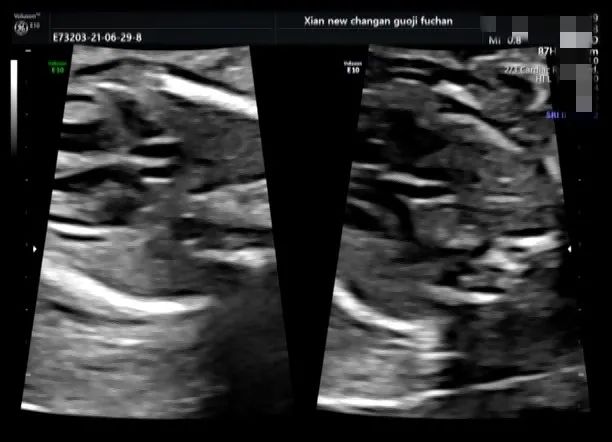

脐带打结是产科胎儿窒息的高危因素之一,利用产前超声检查能够提供准确有价值的诊断依据,我院自 2020 年 10 月至今共产前诊断处 4 例脐带打结。

产科医生向家属告知病情,因 4 例孕妇孕周都在 38W 以上,家属要求行剖宫产手术,娩出婴儿,Apgar 评分:10 分。外观无畸形,脐带中部近胎儿处见真性打结。

脐带真结较为少见,是脐带走形异常或脐带过长在宫内形成环套,胎儿活动穿越环套所致,往往引起不同程度的并发症,易引起胎儿宫内窘迫,严重者可致胎死宫内。

产前超声如怀疑脐带打结,需高度重视,孕期加强监护,注意可疑处脐动脉及脐静脉内径及血流动力学变化,3D 彩色多普勒高分辨仿真血流技术可立体、直观显示脐带形态结构及血流,对脐带打结有一定的诊断价值。